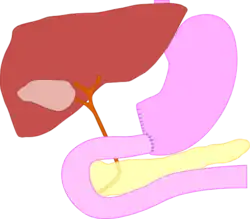

Billroth I, more formally Billroth's operation I, is an operation in which the pylorus is removed and the distal stomach is anastomosed directly to the duodenum.[1][2]

The surgical procedure is called a gastroduodenostomy.[1]